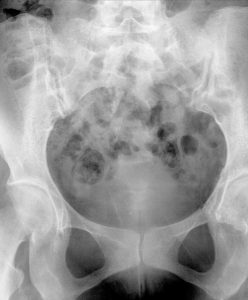

Das Verfahren an sich ist einfach und dauert nur wenige Minuten. Der Arzt injiziert durch die Vagina ein Kontrastmittel in den Uterus. Mithilfe von Röntgenstrahlen wird das Kontrastmittel sichtbar gemacht. Wenn die Eileiter geöffnet sind, fließt das Kontrastmittel in die Eileiter hinein. Da das Kontrastmittel auf dem Röntgenbild gut zu erkennen ist, lässt sich leicht feststellen, ob sich die Eileiter mit der Flüssigkeit füllen oder nicht.